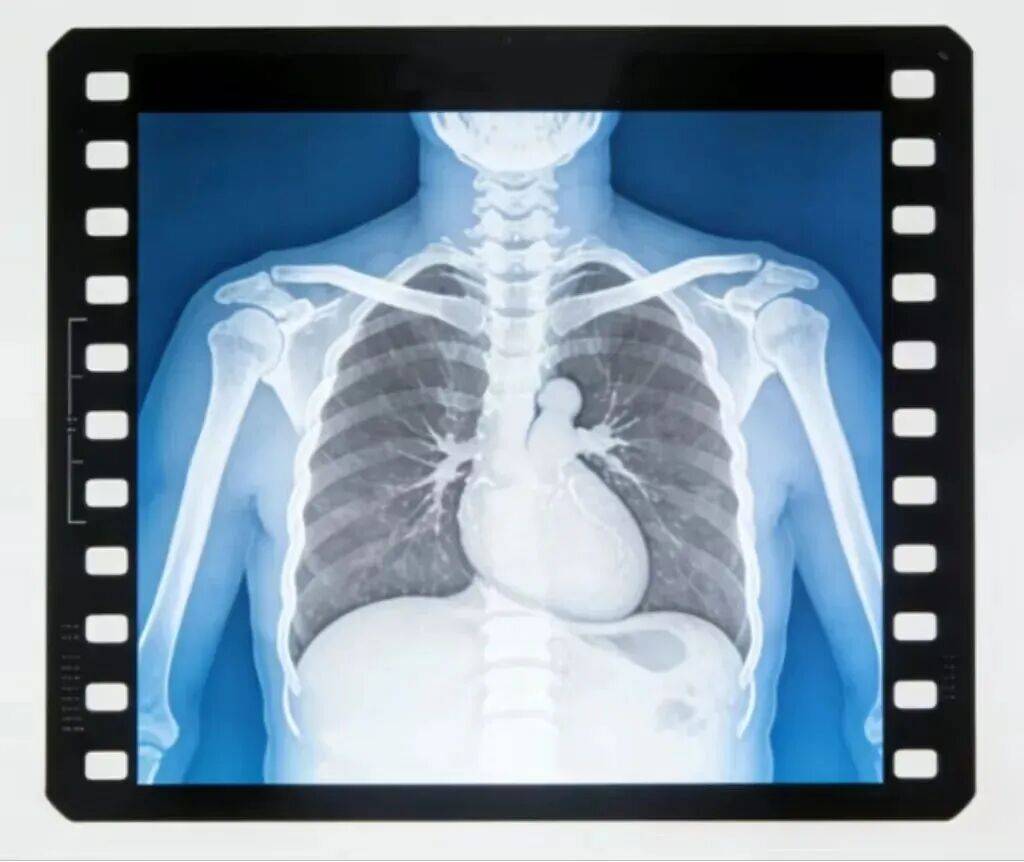

医疗照射应合理必要

医疗照射是普通人接触电离辐射最主要的途径之一,像X光片、CT、核素治疗等检查和治疗手段,都会产生一定剂量的电离辐射。但这并不意味着我们要拒绝所有医疗照射,而是要在医生指导下,做到“合理必要”。